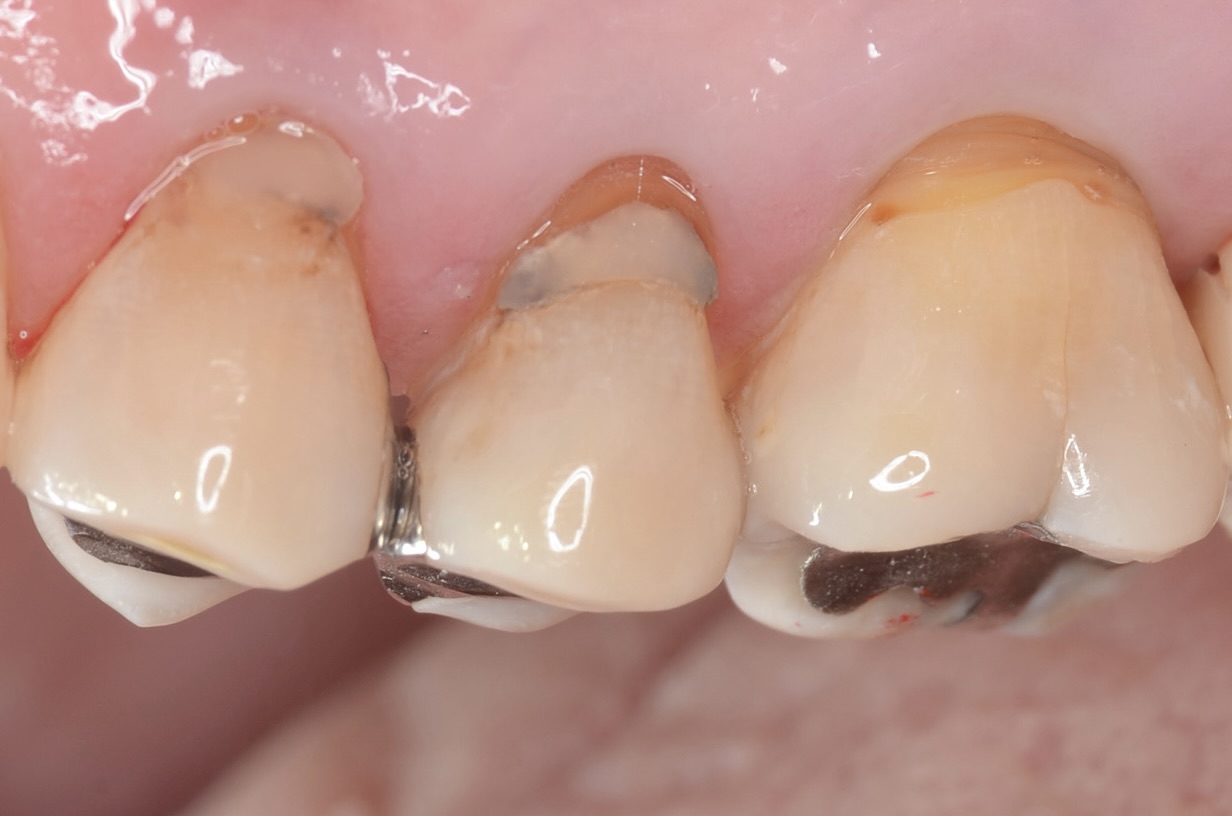

側方面観

歯頸部に古いレジンが充填されており虫歯になっています。 -

歯頸部の虫歯も打イレクトボンディングで治療しました。 -

口蓋側面観

滑らかな曲線でフロスも引っかからないです。